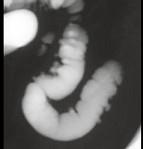

男,52岁,习惯性便秘2年余,结合图像,应诊断为 ( )A.溃疡性结肠炎B.结肠憩室病C.假膜性结肠炎D.结肠息肉病E.结肠转移瘤

问题 男,52岁,习惯性便秘2年余,结合图像,应诊断为 ( )

选项 A.溃疡性结肠炎 B.结肠憩室病 C.假膜性结肠炎 D.结肠息肉病 E.结肠转移瘤

答案 B